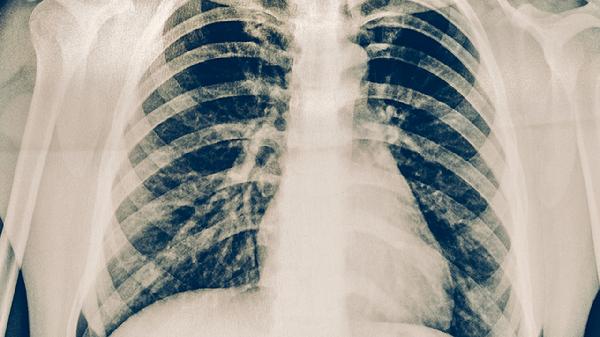

支原体肺炎吃什么药最有效

支原体肺炎患者可在医生指导下使用罗红霉素胶囊、阿奇霉素片、盐酸多西环素片、左氧氟沙星片、盐酸莫西沙星片等药物进行治疗,有助于控制感染并缓解症状。